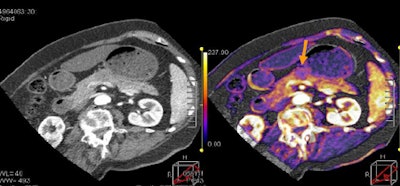

![]()  |

| Tumor and pancreas head are visible on tumor map, with PET image for comparison. All images courtesy of Dr. Sonja Kandel. |